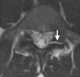

Pars interarticularis defect

Spondylolysis (spon-dee-low-lye-sis) is defined as a defect or stress fracture in the pars interarticularis of the vertebral arch. The vast majority of cases occur in the lower lumbar vertebrae (L5), but spondylolysis may also occur in the cervical vertebrae. [Source: Wikipedia ]